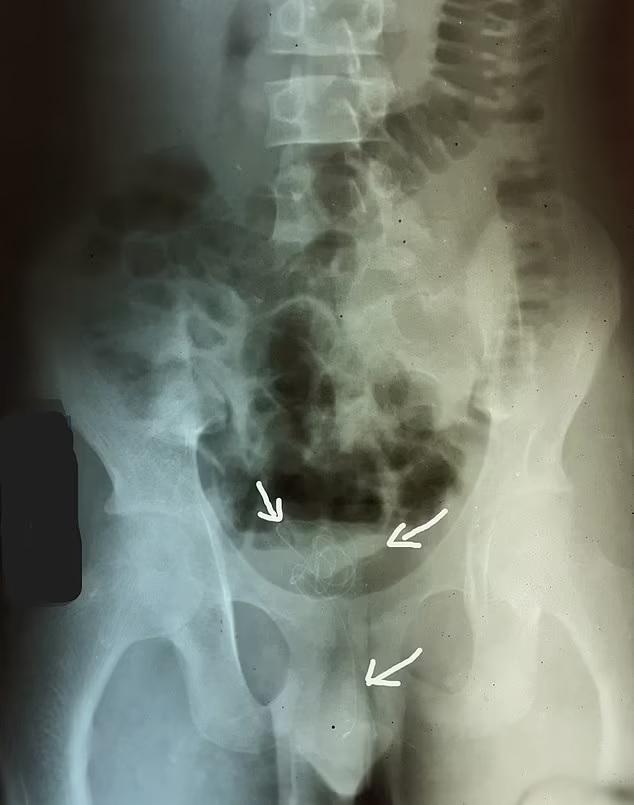

精神病學期刊《Psychiatry Research Case Reports》刊登了一個案,指斯里蘭卡一名17歲少年,因下腹疼痛和排尿困難求醫。X光一照發現他陰莖有異物,醫生最後從其陰莖取出一條8吋長電線。個案刊登在精神病學期刊,因少年向醫生坦承為了性快感,塞異物入陰莖,並沉迷其中,每天這樣自慰3次。醫生將他轉介到精神科醫生治療這種塞異物的「性癮」。

報道指那名少年忍痛9天才去求醫,醫生為他取出電線後,他沒有其他健康問題。他入院後數天才告訴醫生,在過去兩年來一直有這種自慰習慣,通常都能夠取出異物。他出現自慰上癮的跡象,承認每天這樣做3次,想「斷癮」但卻難以自控。塞異物入生殖器官非常危險,有機會引起嚴重感染,導致膀胱組織壞死。據悉,那名少年有社交恐懼並害怕拍拖,心理醫生向那名少年開了一種抗抑鬱藥,治療他的性欲錯亂症,但自他出院後與其失去聯絡,他也未有再尋求心理治療,未知他能否控制性癮。